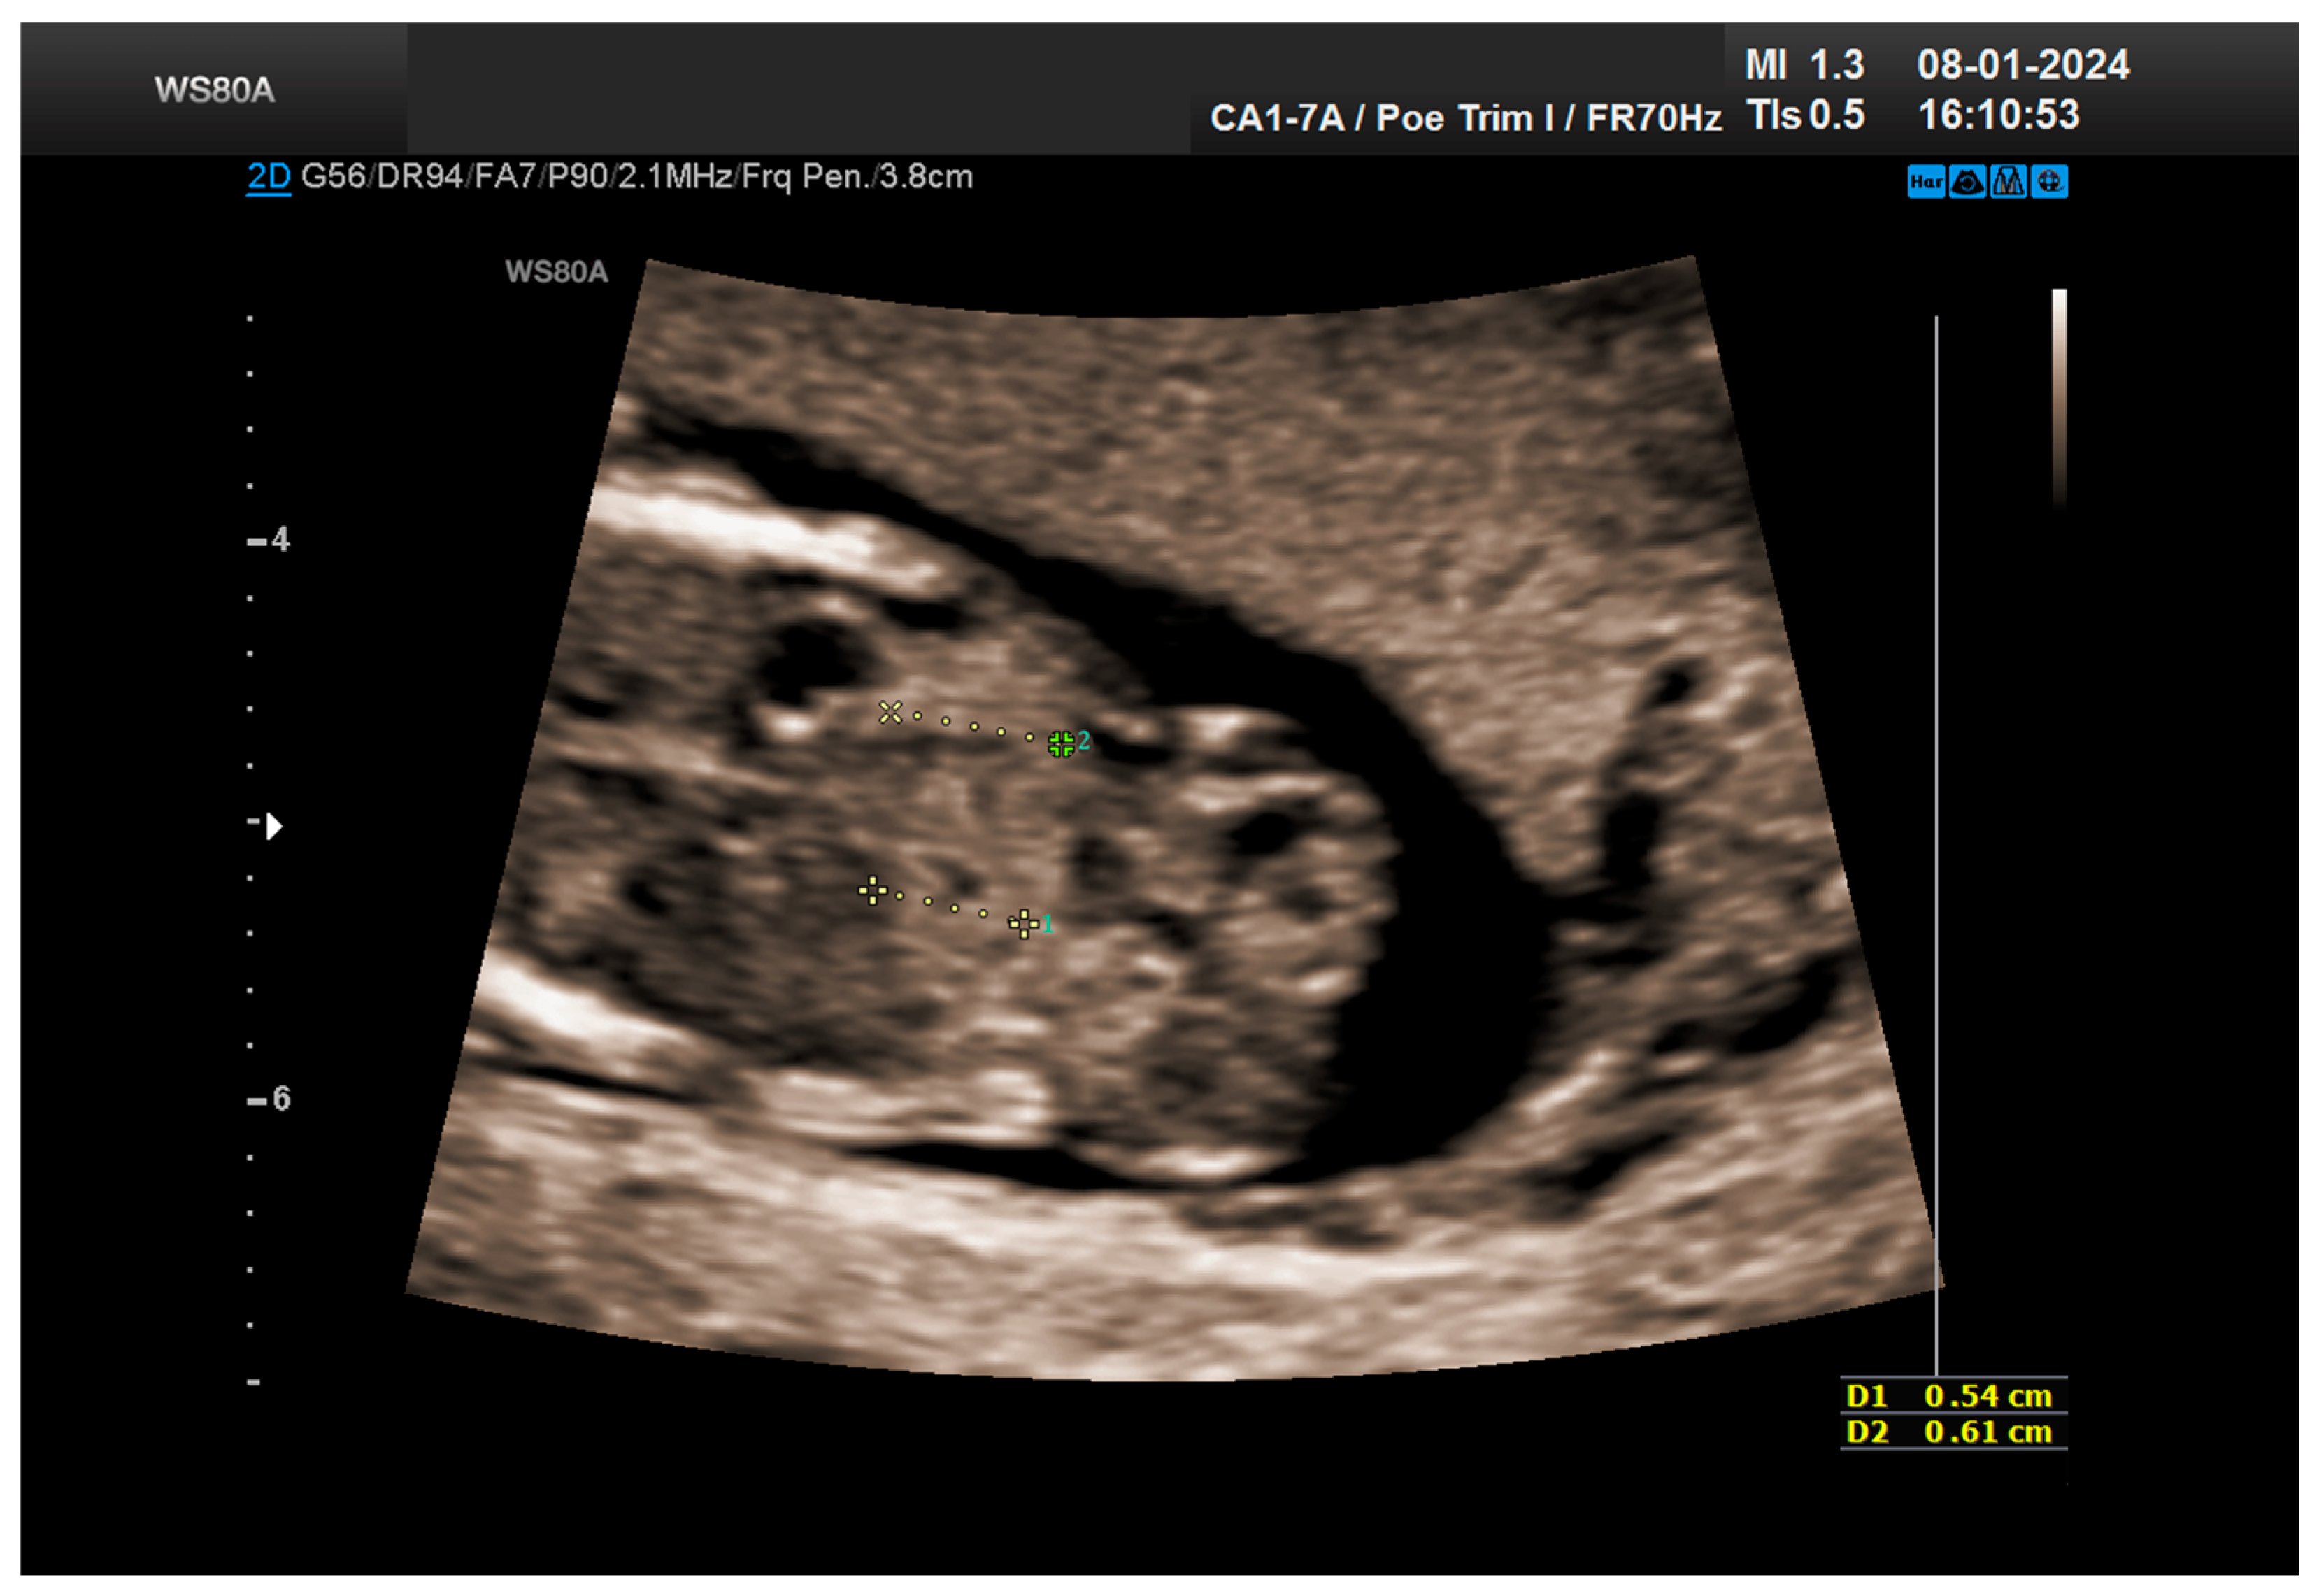

The combined test result indicated a low risk for trisomies, preeclampsia, and intrauterine growth restriction. However, during the ultrasound examination, the absence of the right renal tissue in the right parasagittal sections was noted (Figure 1). Examination of the embryo in axial sections demonstrated the presence of a relatively well-defined acoustically heterogeneous echogenic mass situated anterior to the spine, in sonographic contact with the renal tissue image correctly occupying the left lumbar fossa (Figure 2). Those aspects suggested the existence of a renal anomaly of crossed fused renal ectopia. No other embryonic anomalies were detected, the bladder image was present, and the amniotic fluid volume was normal. The calculated gestational age corresponded to the ultrasound estimate. The suspicion of crossed fused renal ectopia was maintained during a subsequent reevaluation at 17 weeks of pregnancy (Figure 3 and Figure 4).

Figure 2. Crossed fused kidneys at 13 weeks.

Figure 3. The two kidneys are clearly visualized: the right one, ectopic, fused with the left kidney, normally positioned—ultrasonography revaluation at 17 weeks.